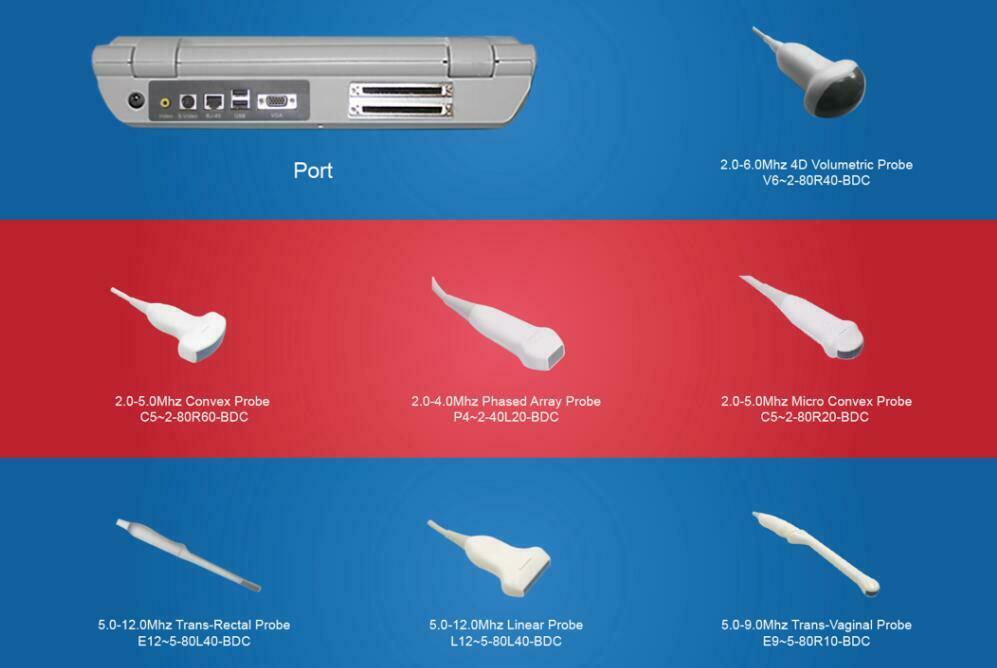

One of the key features of the Laptop Color Doppler Ultrasound is its portability. This means you can easily transport it between examination rooms or even take it off-site when necessary. Despite its compact size, it offers robust capabilities that rival larger, stationary units. Medical professionals appreciate the balance of convenience and high performance it offers.

The user interface of the Laptop Color Doppler Ultrasound is designed for ease of use. It features a high-resolution display, intuitive controls, and customizable settings. This makes it accessible for both new and experienced Sonographers. The device runs on powerful software that supports various diagnostic applications, ensuring versatility in its use. Therefore, it can be used for a wide range of procedures, from obstetric exams to cardiac assessments.

Connectivity options are also impressive. The Laptop Color Doppler Ultrasound can easily connect to other devices and health information systems. This facilitates seamless data transfer and integration, enhancing workflow efficiency and patient record management. The ability to share diagnostic images and data quickly can significantly improve patient outcomes.